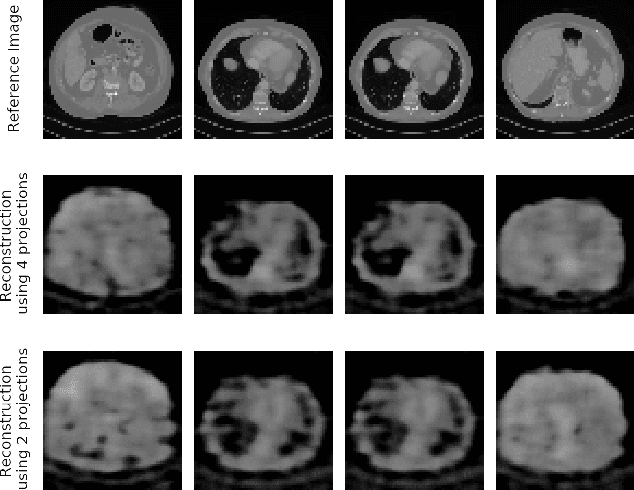

In computed tomography (CT), automatic exposure control (AEC) is frequently used to reduce radiation dose exposure to patients. For organ-specific AEC, a preliminary CT reconstruction is necessary to estimate organ shapes for dose optimization, where only a few projections are allowed for real-time reconstruction. In this work, we investigate the performance of automated transform by manifold approximation (AUTOMAP) in such applications. For proof of concept, we investigate its performance on the MNIST dataset first, where the dataset containing all the 10 digits are randomly split into a training set and a test set. We train the AUTOMAP model for image reconstruction from 2 projections or 4 projections directly. The test results demonstrate that AUTOMAP is able to reconstruct most digits well with a false rate of 1.6% and 6.8% respectively. In our subsequent experiment, the MNIST dataset is split in a way that the training set contains 9 digits only while the test set contains the excluded digit only, for instance "2". In the test results, the digit "2"s are falsely predicted as "3" or "5" when using 2 projections for reconstruction, reaching a false rate of 94.4%. For the application in medical images, AUTOMAP is also trained on patients' CT images. The test images reach an average root-mean-square error of 290 HU. Although the coarse body outlines are well reconstructed, some organs are misshaped.